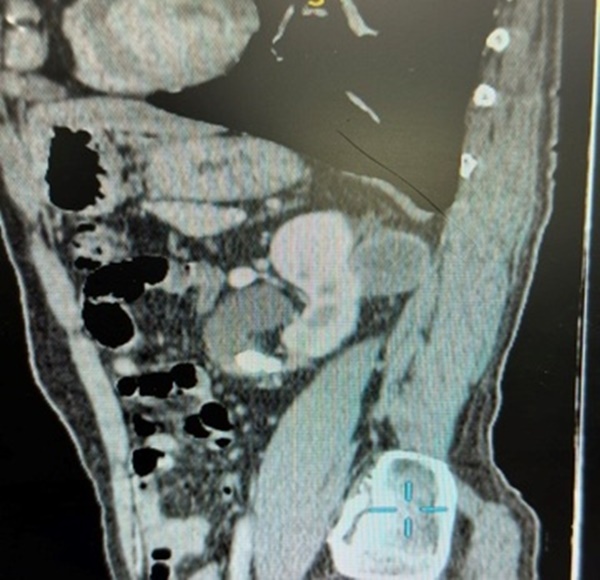

Người đàn ông cho hay đã được thực hiện nội soi niệu quản trái tán sỏi 3 năm. Tại bệnh viện này, kết quả khám và xét nghiệm cận lâm sàng cho thấy bệnh nhân rung thận trái, ấn điểm đau niệu quản trái 1/3 trên. Hình ảnh CT scan hệ tiết niệu có nang thận trái (36x45 mm), thành dày không đều, ngấm thuốc sau tiêm, nang thận phải Bosniak I, sỏi niệu quản trái 1/3 trên gây giãn thận độ 2.

Hình ảnh nang thận trái Bosniak IV và sỏi niệu quản trái 1/3 trên. Ảnh: BVCC.